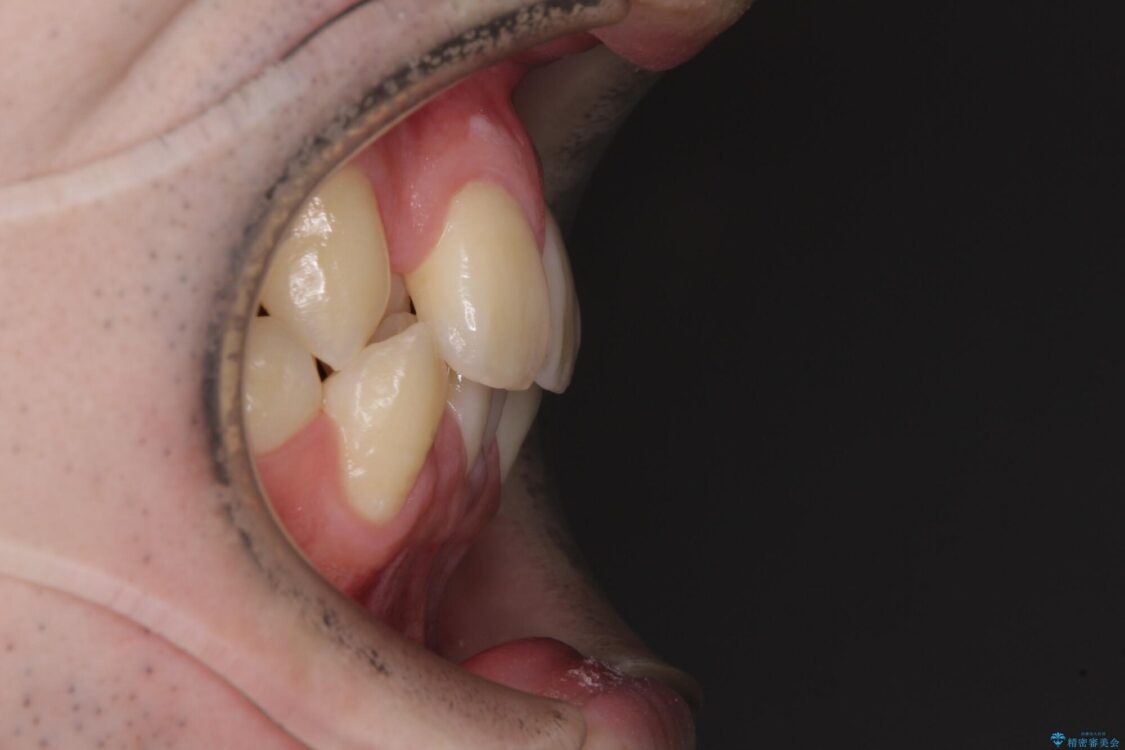

治療前

• 全顎的なクロスバイト 補助装置を用いてワイヤー矯正 治療前画像